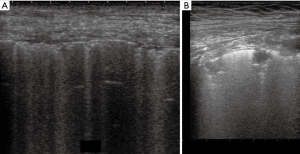

Thickened (but anatomically intact) secondary interlobular septa may act as acoustic traps where specific frequencies give rise to separated, uniform, bright and long B-lines, without spared areas (septal pattern, see Figures 1 and 2), especially in early CPE (Figure 1) (17). In ARDS subpleural random peri and intralobular distortion may explain the appearance of acoustically permissive irregular channels, different arrangements of B-lines, pleural irregularities, consolidations, and inhomogeneous isolated air spaces. Inhomogeneous edema, alveolar collapses and pulmonary fibrosis contribute to the development of the pleural irregularities that are seen in ultrasound and to the reduction of the pulmonary compliance and pleural sliding in ARDS (Figure 3) (9).

In other words, in ARDS an early complex tissue arrangement is at the basis of the very variable images that can be seen in sonography. On the contrary, the appearance of typical septal B-lines (shown in early CPE) is not usual in ARDS, when discrete septal thickening surrounded by anatomically normal air spaces is not present.

In practical terms, therefore, the ultrasound picture of early CPE can be said to be characteristic, as is the ultrasound picture of ARDS in day 3, due to the presence of septal pattern in CPE and of inhomogeneous SIS and consolidations in ARDS, respectively. In late CPE, when alveolar flooding takes place, the sonographic picture tends to become confused with that of early ARDS, which in many cases, however, shows spared areas. The association of diffuse interstitial diseases and CPE is equally confounding.